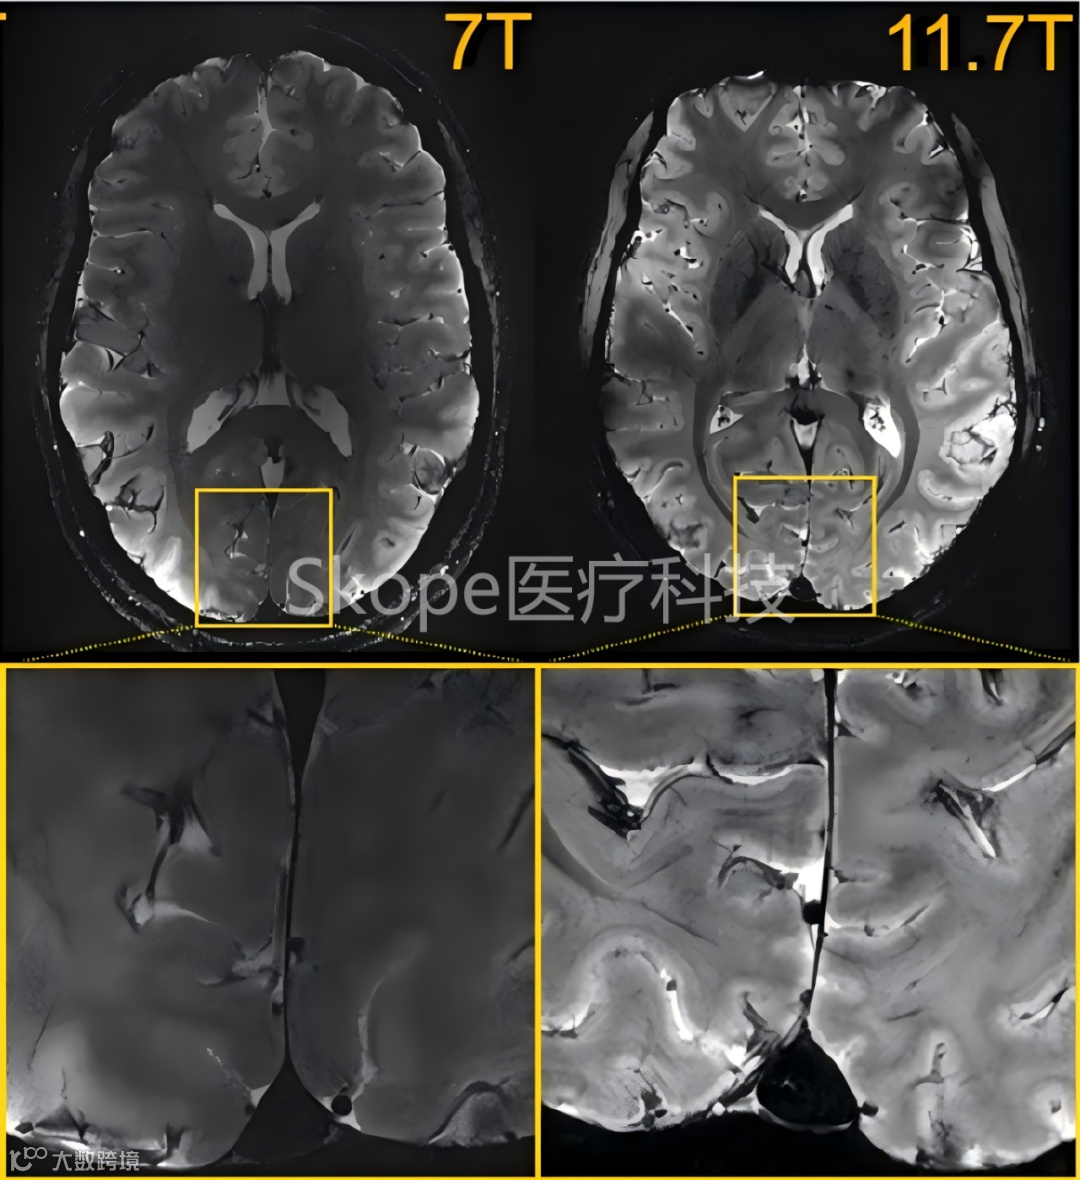

7T和11.7T下取得的T2*加权的二维梯度回波(GRE)轴向图像(不同受试者)

采集参数:分辨率=0.2×0.2×1mm³,FA=27°,TE=20ms,TR=0.6 s,带宽=40 Hz/像素,采集时间4分20秒。

这组图片直观地反映出超高场成像在图像清晰度和细节方面的显著优势。

c. 3T(左)、7T(中)和11.7 T(右)下采集的T2* 加权2D GRE轴向图像

采集时间相同(4分17秒),通过调整采集参数:3、7和11.7 T的FA(°)、TR(ms)和TE(ms)分别为27、750和45;34、950和25;27、600和20;空间分辨率:3、7和11.7 T的平面分辨率分别为0.5、0.325和0.2mm,厚度均为 1 mm来保持相似的对比度噪声比(CNR)。